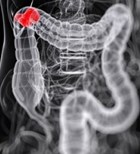

כל אחד יודע כי יש צורך בבדיקת קולונוסקופיה החל מגיל 50. מהי...